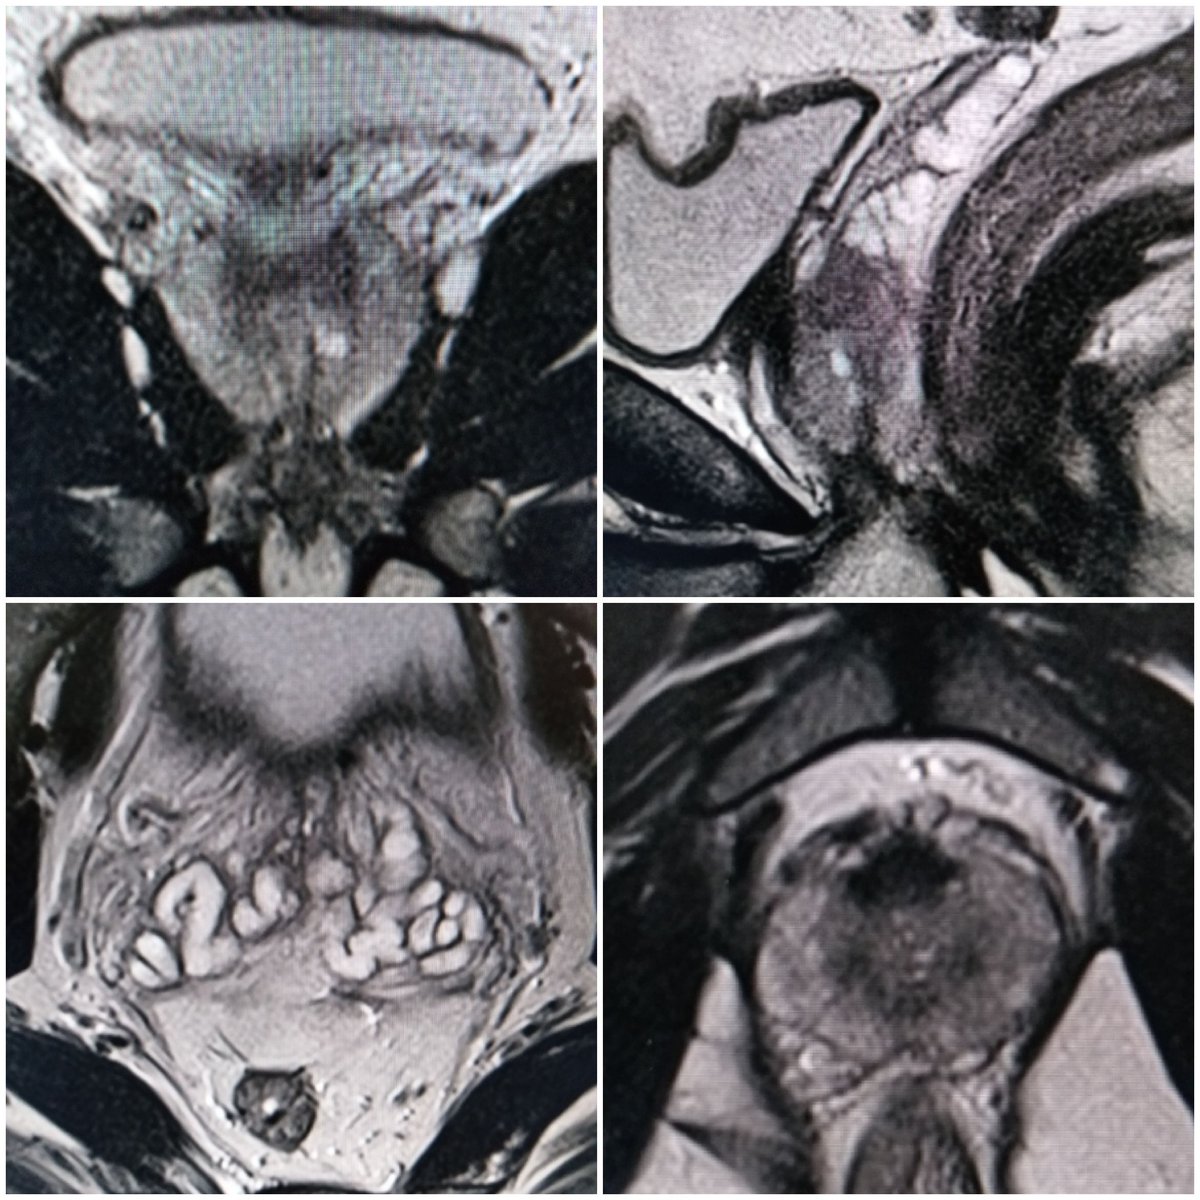

Resonancia Multiparamétrica de próstata. Paciente de 49a, con cambios sugestivos de Prostatitis. DWI sin restriccióny perfusión captación difusa, Pirads 3. #RMmp #próstata #difusión #perfusión #draluisavera

lameliav's tweet image. Resonancia Multiparamétrica de próstata. Paciente de 49a, con cambios sugestivos de Prostatitis. DWI sin restriccióny perfusión captación difusa,  Pirads 3.

#RMmp #próstata #difusión #perfusión #draluisavera